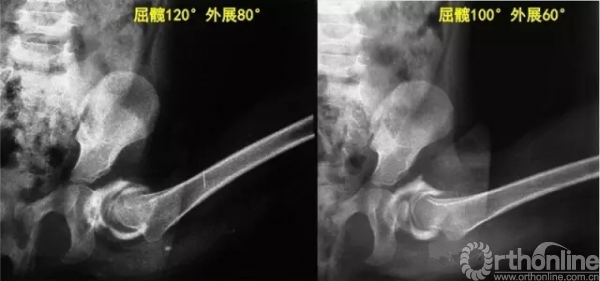

答:1)因为小年龄儿童股骨头大部分是软骨结构,股骨头骨化核在髋脱位时经常“偏外”,因此,根据骨化核位置判断复位质量不可靠;2)不行关节造影的传统“手法复位”,对复位质量的判断仅仅依靠复位时“手感”,而关节造影可以根据造影下头-臼对位情况实时调整屈髋、外展角度,对每个髋关节都找到最理想的对位位置。

问:闭合复位时不是屈髋、外展角度越大头-臼对位越好吗?

答:每个孩子髋关节具体情况都不完全一样,“屈髋、外展角度越大头-臼对位越好”的说法非常主观。